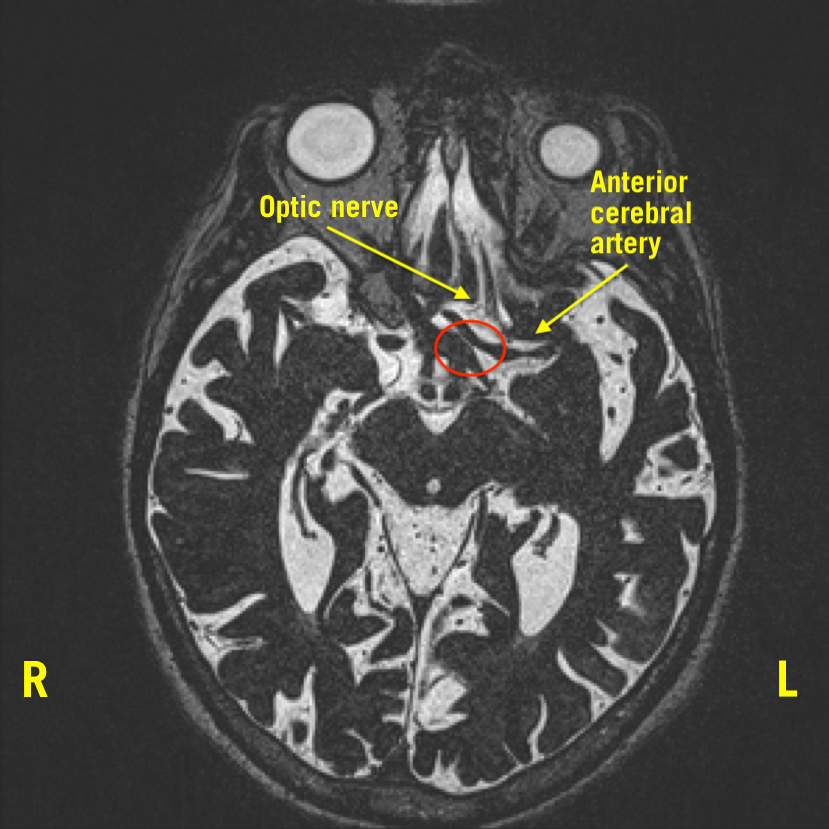

MRI of a patient with NMO showing inflammation (circled in red) of both What Is Optic Nerve Imaging Unusual findings like swelling or buckling of the optic nerve or a bumpy retina. Scans can detect small nerve fiber layer changes of the optic nerve at the micron level. Glaucoma specialists take pictures of the optic nerve to measure the health of your eye and your risk for glaucoma. Developments in optic nerve imaging have specifically improved the care. What Is Optic Nerve Imaging.

From www.hmpgloballearningnetwork.com